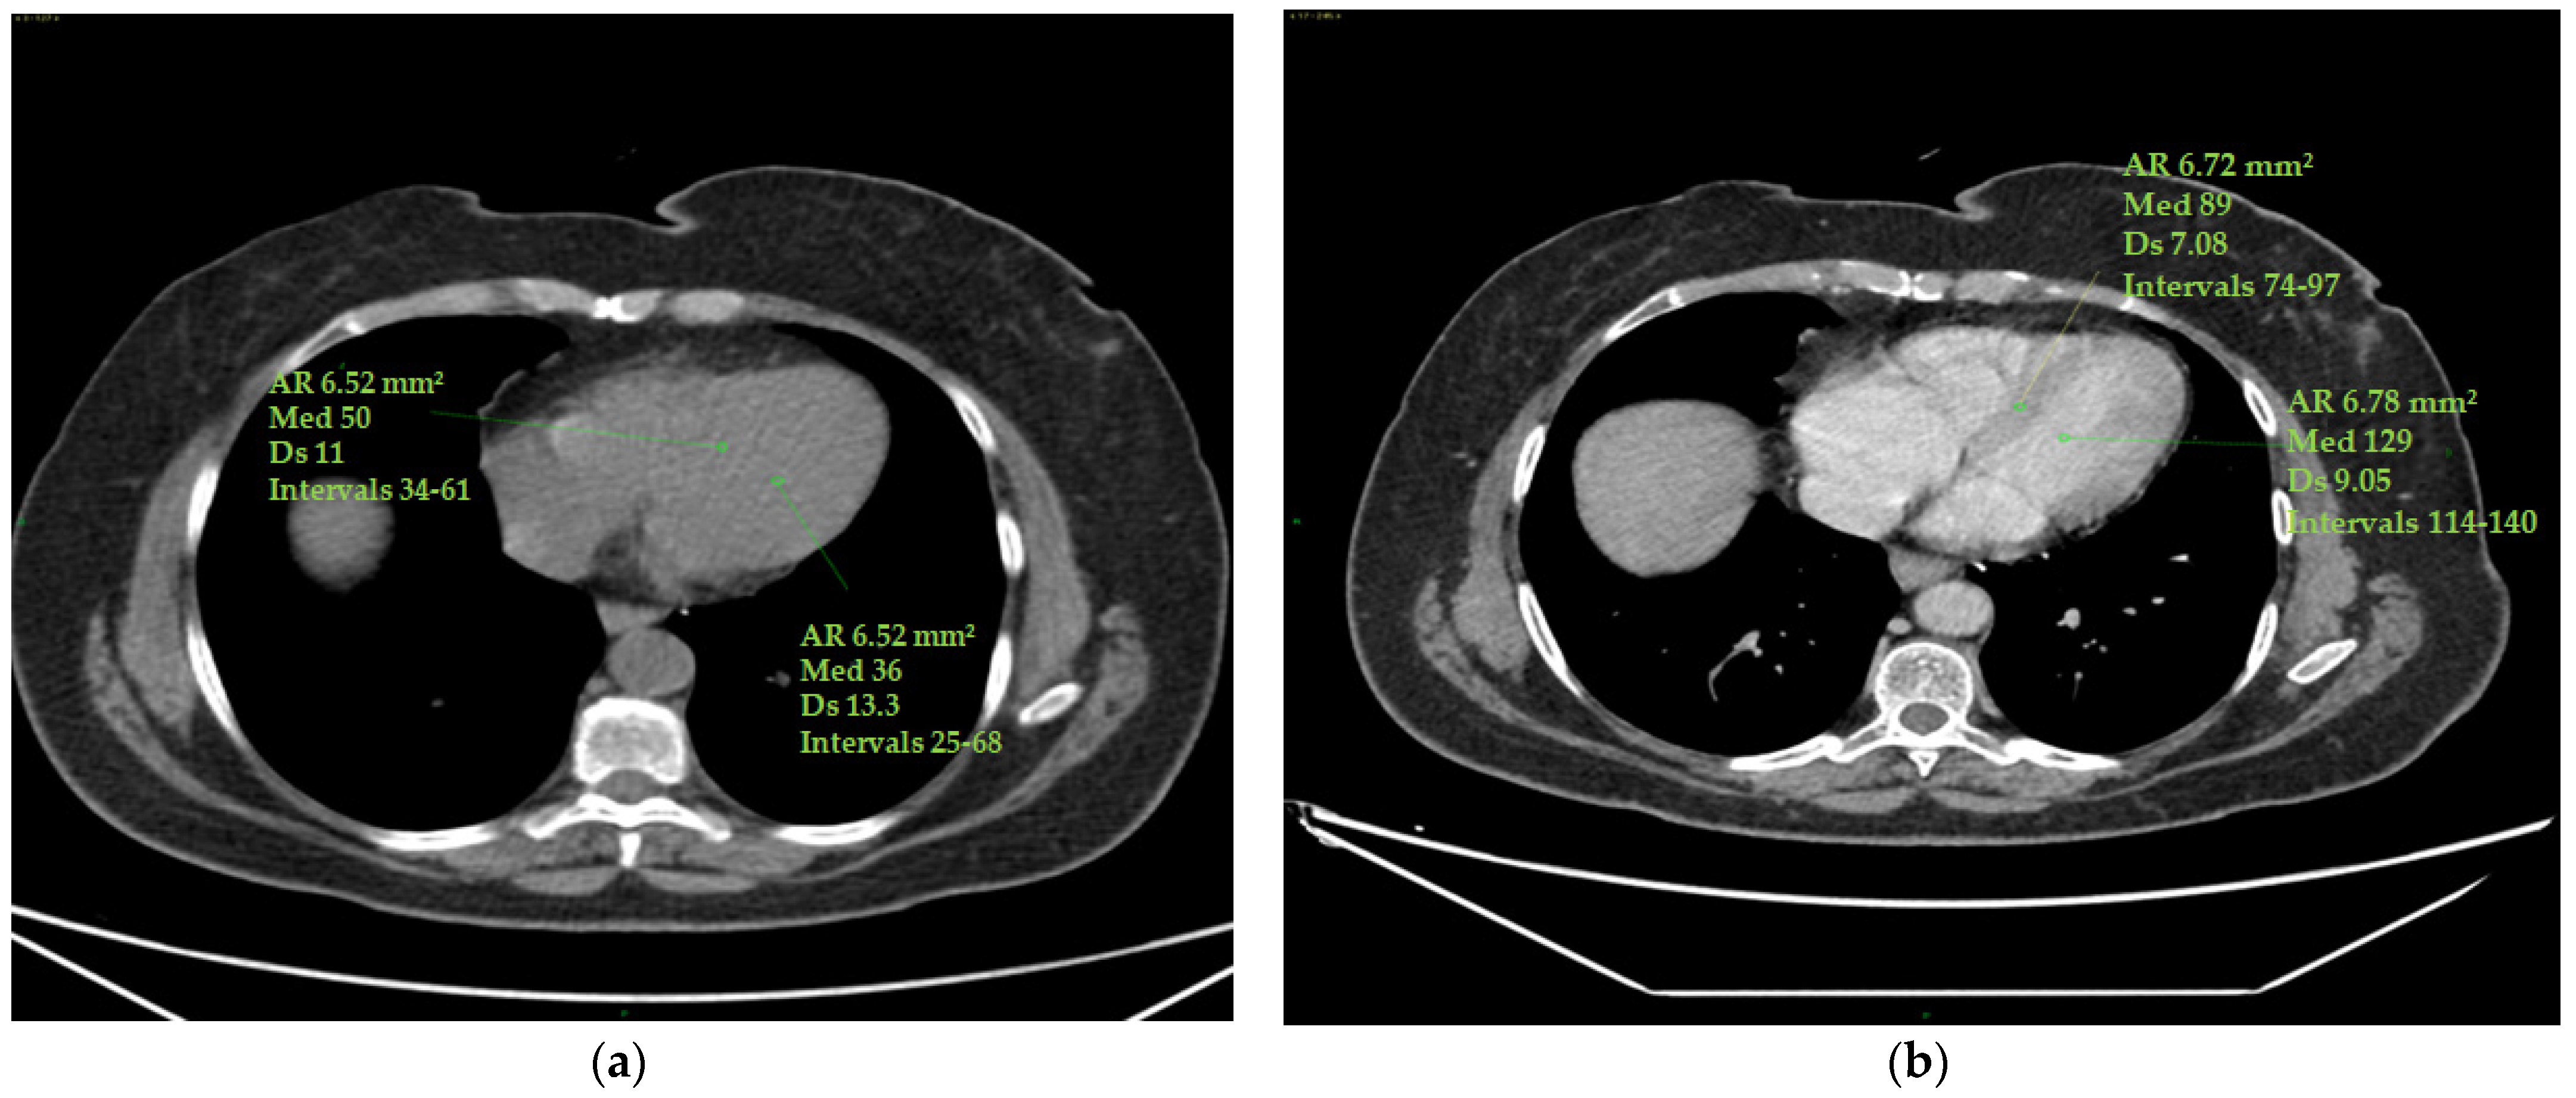

The epicardial adipose tissue (EAT) density was assessed using a specialized workstation (GE Healthcare, General Electric, Boston, MA, USA) at baseline and at the end of therapy. EAT density was measured on basal scans in a 4-chamber projection, at the level of the anterior interventricular sulcus, at the origin of the posterior interventricular artery within the posterior interventricular sulcus and at the level of the cardiac apex (Figure 2).

Figure 2. (ac) Epicardial fat density measurement. Using a 4-chamber projection, epicardial fat density was assessed on axial perspective basal CT scans, using a manually placed ROI (with a mean area of 6 mm2) within the anterior interventricular sulcus (a), posterior interventricular sulcus (origin of the posterior interventricular artery) (b) and cardiac apex (c). The figure shows an example of the area of the region of interest (Ar ROI), the mean (med), the standard deviation (Ds) and the range (intervals) of hounsfield units measured.